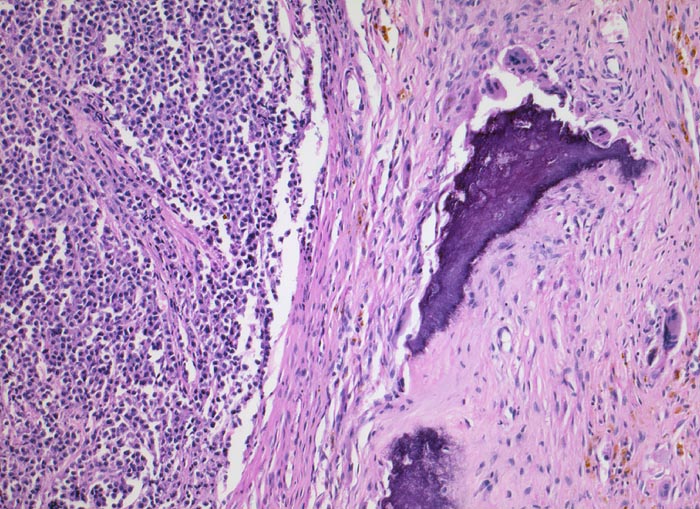

• Knochenmarkstanze mit nodulärer Hyperzellularität des blutbildenden Marks.

• Keine wesentliche Osteopenie.

• In den hyperzellulären Arealen dichte Rasen neoplastischer atypischer Plasmazellen.

• Ausserhalb der Plasmazellrasen findet sich spärlich residuelles blutbildendes Knochenmark.